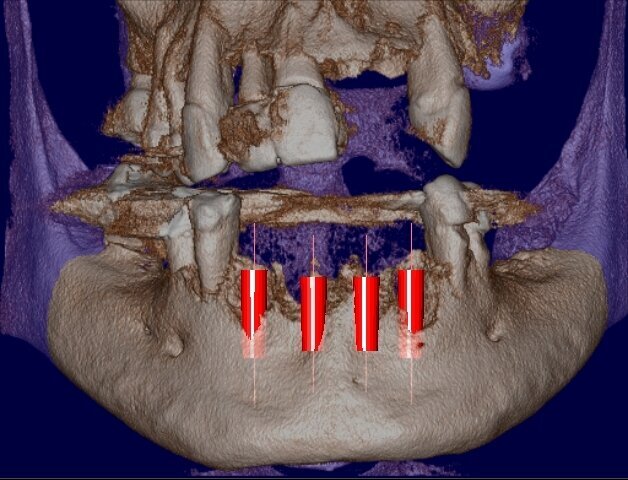

Viene presentato il caso di un paziente (maschio, 57 anni) inquadrato nosologicamente come ASA 1 e riferito alla nostra osservazione per la riabilitazione implantoprotesica di un’area edentula in mandibola anteriore (Fig. 1). Le indagini radiografiche di 1° e 2° livello (ortopantomografia e CBCT) evidenziano una marcata atrofia ossea di tipo combinato (classificabile come grado 3 sec. Seibert) che controindica l’inserimento di impianti osteointegrati (Fig. 2). Considerato il notevole riassorbimento della cresta ossea, per ridurre il rischio di incidenti intraoperatori e poter pianificare al meglio l’intervento chirurgico, viene simulato il posizionamento di 4 impianti Resista IA3413 (Resista, Via F.lli Di Dio, 68 – Omegna, VCO) tramite il software per ricostruzione tridimensionale Real Guide Ver. 5.0 (3Diemme, Como).

Gli impianti vengono presi dalla libreria Resista presente sul software Real Guide Ver. 5.0 (3Diemme, Como) e posizionati con la corretta angolazione e profondità nella cresta atrofica da riabilitare: la ricostruzione tridimensionale prevede una parziale esposizione delle fixtures (Figg. 3, 4). In base ai dati assunti dalla simulazione, viene quindi programmato un intervento di Rigenerazione Ossea Guidata (G.B.R.) con membrane di tipo non riassorbibile in PTFE associata a un innesto di tipo composito (costituito da particolato osseo autologo in chips miscelato a un biomateriale di origine eterologa) e al contemporaneo inserimento di 4 impianti osteointegrati. La profilassi antibiotica è iniziata un’ora prima dell’intervento (amoxicillina/acido clavulanico, Augmentin, Glaxo-SmithKline, Verona, Italia, 2 g 1 ora prima della chirurgia e poi 1 g ogni 12 ore per 6 giorni).

Fig. 4 - Simulazione preimplantare che evidenzia la limitata disponibilità ossea in senso verticale e orizzontale.